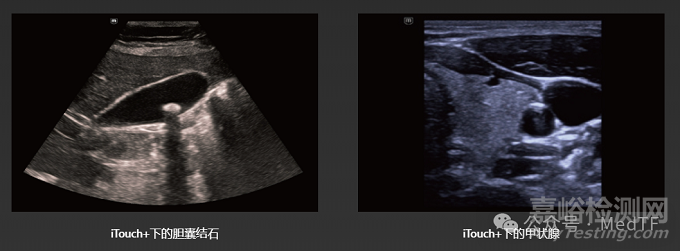

iTouch+: 一鍵切換檢查模式并優(yōu)化圖像質(zhì)量,自動切換檢查模式,并優(yōu)化圖像質(zhì)量,顯著減少手動操作,使掃查更容易。